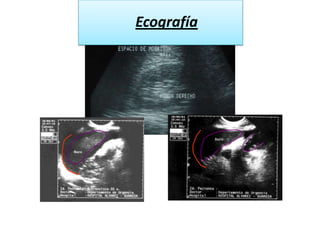

EcografíaLíquido libre abdominal